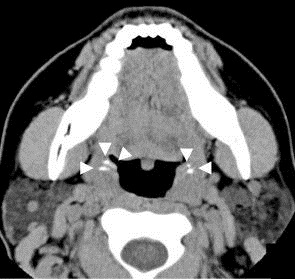

영상 진단 기술은 이물질, 전위된 치아 또는 석회화된 혈관으로 오인될 수 있는 방사선 불투과성 덩어리를 식별할 수 있다. CT 스캔은 편도 영역에서 비특이적인 석회화된 이미지를 나타낼 수 있다. 감별 진단은 급성 및 만성 편도선염, 편도선 비대, 편도 주위 농양, 이물질, 정맥석, 이소성 뼈 또는 연골, 림프절, 육아종 병변 또는 이글 증후군 (긴 경상 돌기)의 맥락에서 경돌설골 인대의 석회화와 함께 이루어져야 한다.[18]

일반적인 편도결석보다 훨씬 드문 거대 편도결석은 편도 주위 농양 및 편도 종양을 포함한 다른 구강 질환으로 오인될 수 있다.[17] CT 스캔은 편도 영역에서 비특이적인 석회화된 이미지를 나타낼 수 있다. 감별 진단은 급성 및 만성 편도선염, 편도선 비대, 편도 주위 농양, 이물질, 정맥석, 이소성 뼈 또는 연골, 림프절, 육아종 병변 또는 이글 증후군의 맥락에서 경돌설골 인대의 석회화와 함께 이루어져야 한다.[18] 편도결석의 감별 진단에는 이물질, 석회화된 육아종, 악성 종양, 비대해진 측두 경상 돌기 또는 드물게 배아 잔존물에서 유래된 고립된 뼈가 포함되며, 이는 일반적으로 새궁에서 기원한다.[19]